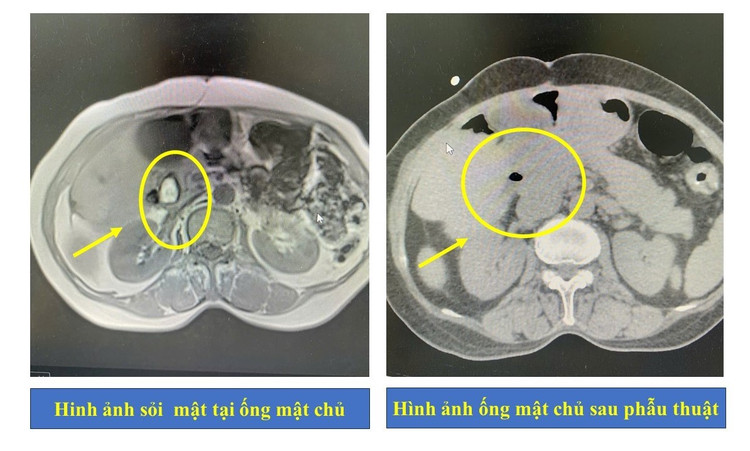

Sau khi thực hiện các cận lâm sàng cần thiết, kết quả cho thấy người bệnh bị nhiễm trùng đường mật, tắc mật do sỏi tại ống mật chủ.

Hình ảnh ống mật chủ của người bệnh trước và sau phẫu thuật - Ảnh BVCC

Người bệnh được chuyển đến Khoa Ngoại Tiêu hóa - Gan mật và chỉ định dẫn lưu đường mật qua da. Sau 5 ngày điều trị tích cực, tình trạng tắc mật và nhiễm trùng đã được cải thiện, người bệnh tiếp tục được chỉ định phẫu thuật tán sỏi đường mật qua da bằng laser – phương pháp đang được ứng dụng rộng rãi tại Bệnh viện Đa khoa tỉnh Phú Thọ.

Đặc biệt, trong quá trình thực hiện tán sỏi đường mật qua da bằng laser, các bác sĩ đã phát hiện một con giun nằm trong ống mật. Đây là trường hợp rất hiếm gặp, đòi hỏi kỹ thuật xử lý linh hoạt và chính xác. Nhờ năng lực chuyên môn cao cùng kinh nghiệm dày dặn, ê kíp đã loại bỏ triệt để sỏi và dị vật là con giun đũa dài khoảng 15cm ra khỏi cơ thể người bệnh.